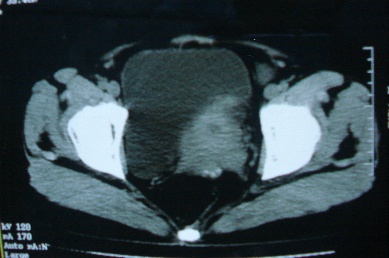

ct10755,女,48岁。感腹胀一周入院。

考虑右侧卵巢囊腺癌并腹腔转移、子宫肌瘤

感觉像是2个病变融合:双侧附件囊腺瘤?

考虑右侧卵巢囊腺癌并腹腔转移可能性大、子宫肌瘤

支持:右侧卵巢囊腺癌并腹腔转移,或囊腺瘤破裂腹腔种植。

支持:右侧卵巢囊腺癌并腹腔转移、腹水、盆腔积液。

支持右侧卵巢囊腺癌并腹腔转移(大量腹水)。